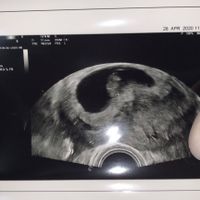

4Qualcuna che se ne intende? Io di angoli non ho capito nulla provate a indovinare , forse il 23 agosto riuscirò a vedere il sesso e vi dirò se avete indovinato!!! !

Ragazze sono di 7 settimane oggi ed ho appena fatto l'ecografia, si capisce cosa potrebbe essere in base al metodo Ramzi? 😊😊 Ho già un maschietto di 2 anni

Oggi ho fatto il Gtest e tra dieci giorni circa oltre agli altri esami avrò il risultato anche del sesso, così un po’ per divertirci a sfatare miti volevo allegare 2 ecografie una di 8 settimane fatta...